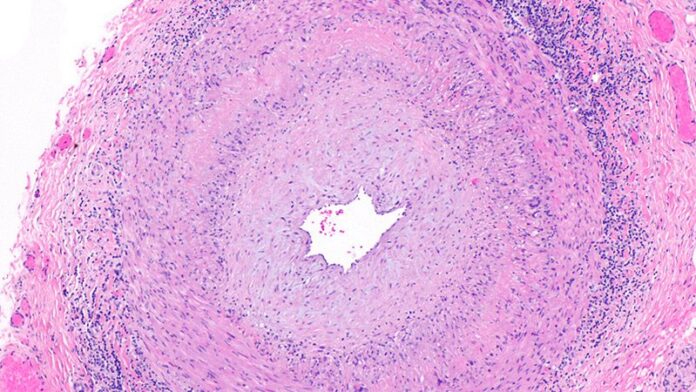

A key issue in GCA diagnosis is the need to confirm inflammation, Chévez-Barrios said. “The surgeon must obtain a significant portion of the artery, and the pathologist should review several sections and levels of the tissue to confidently say whether there is inflammation or no.”

In addition, the American College of Rheumatology recommends that patients with a high suspicion of GCA should begin corticosteroids as soon as laboratory studies are obtained; “As a result, if a TAB is performed after treatment begins, the typical active pattern of inflammation in the artery changes,” Chévez-Barrios said. “This further challenges the diagnosis in a frozen section setting because of the need for immunohistochemistry.” Although frozen sections are feasible in specialized settings such as the Mayo Clinic, most patients receive adequate diagnosis and treatment based on permanent sections.